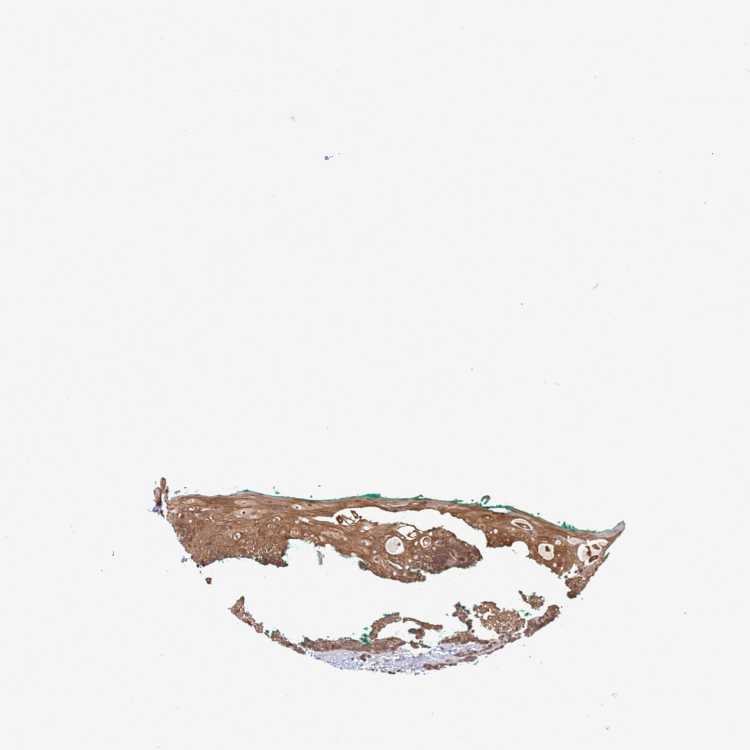

TISSUE PRIMARY DATA ORAL MUCOSA Show tissue menu

ORAL MUCOSA - Antibody stainingi

Antibody staining in the annotated cell types in the current human tissue is reported as not detected, low, medium, or high, based on conventional immunohistochemistry profiling in selected tissues. This score is based on the combination of the staining intensity and fraction of stained cells.

Each image is clickable and will lead to virtual microscopy that enables deeper exploration of all samples and also displays staining intensity scores, fraction scores and subcellular localization as well as patient and tissue information for each sample.

Antibody HPA046577Antibody HPA049664

Squamous epithelial cells MediumMedium